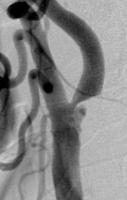

頸動脈ステント留置術

狭くなり血流が悪くなってしまった頸動脈に、ステントと呼ばれる金属性のメッシュ状の筒を留置して血管を拡張させ、血流を回復させる手術です。